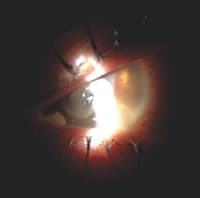

Figure 4. CLARE |

Slit lamp examination OS revealed grade 2 circumlimbal injection and multiple, small peripheral infiltrates that didn't stain with fluorescein. No anterior chamber reaction was evident. We diagnosed CLARE OS (Figure 4) and initiated treatment with an antibiotic/steroid combination drop qid OS for one week. We advised her to discontinue contact lens wear until follow up. Examination one week later revealed that all signs and symptoms had resolved. The conjunctiva was white and quiet, and all the infiltrates had cleared without scarring.